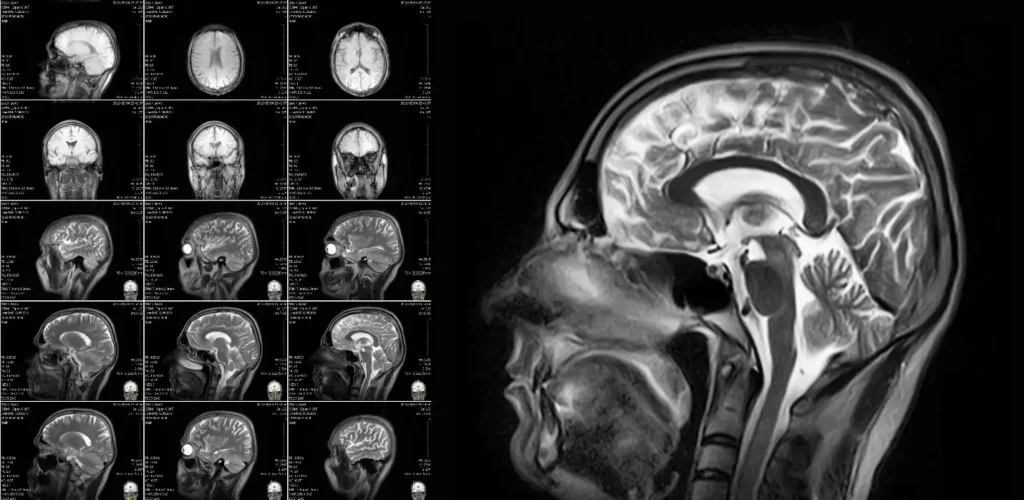

Drug Delivery System Imaging: Magnetic Resonance Imaging (MRI)

MRI is a powerful imaging technique that produces high-resolution, three-dimensional images without the use of ionizing radiation. It offers exceptional soft tissue contrast, making it invaluable for diagnosing and monitoring conditions in the brain, spine, joints, and other soft tissues. MRI’s capabilities can be extended to Functional MRI (fMRI), which assesses metabolic changes and brain activity, enabling the precise delivery of drugs for neurological conditions. When drugs are linked to MRI-visible agents, such as magnetic nanoparticles, MRI can track drug distribution and monitor controlled release mechanisms, providing real-time feedback on accuracy and drug delivery in targeted tissues.

While MRI excels at imaging soft tissues, it is less effective for visualizing bones or air-filled and fluid-filled organs, such as the lungs or gastrointestinal tract. Additionally, MRI is incompatible with certain metallic implants or devices (e.g., pacemakers, cochlear implants) unless they are MRI-compatible.

The use of MRI in drug delivery procedures introduces several constraints. Drug delivery devices must be MRI-compatible to prevent interference and ensure patient safety, requiring the use of non-ferromagnetic materials such as compatible needles and catheters. The design of these devices must account for the magnetic field and radiofrequency pulses involved in MRI.

Furthermore, MRI systems are expensive to purchase and maintain, limiting their availability, particularly for drug delivery procedures requiring intra-operative MRI suites. MRI scans also take longer than other imaging modalities, posing a challenge for time-sensitive procedures.

Despite the higher costs and limited availability, MRI remains critical when high-resolution imaging or fMRI is required for effective therapy delivery. A notable example of a drug delivery device is the ClearPoint Neuro Navigation System, which uses real-time MRI guidance for precise catheter placement in the brain, enabling targeted drug delivery in the treatment of Parkinson’s disease. Especially in these instances, in which MRI is absolutely required, it is favorable to design systems and processes that minimize the time spent inside the MRI scanner by shifting parts of the drug administration process outside of the MRI environment. This helps improve accessibility to the procedure and helps more patients gain access to these treatments.